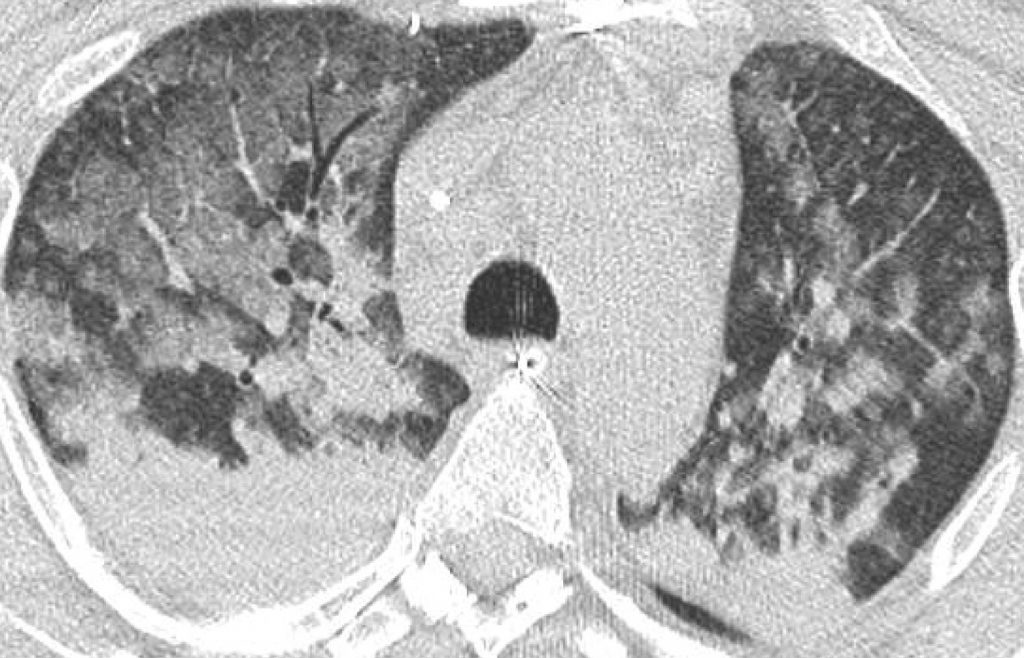

Fig. 93.3. Scanner thoracique.

Œdème pulmonaire non cardiogénique dans le cadre d’un syndrome de détresse respiratoire aiguë (SDRA). Opacités postérieures bilatérales qui correspondent non pas à de l’épanchement pleural mais à des condensations parenchymateuses déclives. Les régions antérieures et moyennes restent aérées malgré des plages de « verre dépoli » assez importantes.

Source : CERF, CNEBMN, 2022.